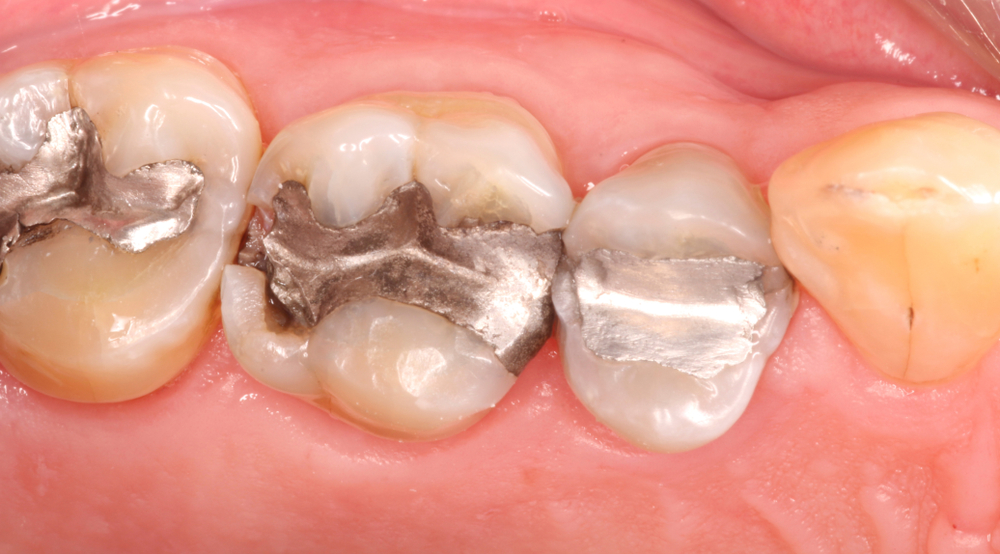

水銀に関する水俣条約(水俣条約)は11月3日から7日、第6回締約国会議を開催。同条約の附属書Aを改正し、2034年までに歯科用水銀アマルガムの使用を段階的廃止することを採択した。同条約には153カ国が加盟している。

歯科用水銀アマルガムは、…